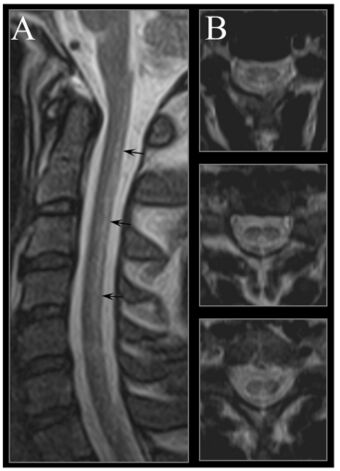

| Image of the cervical spinal cord in vitamin B12 deficiency showing subacute combined degeneration. (A) The midsagittal T2 weighted image shows linear hyperintensity in the posterior portion of the cervical tract of the spinal cord (black arrows). (B) Axial T2 weighted images reveal the selective involvement of the posterior columns. |

A further complication of severe deficiency is the neurological complex known as subacute combined degeneration of spinal cord.[25][26] also myelosis funicularis,[27] or funicular myelosis.[26] This complex consists of the following symptoms:

Severe vitamin B12 deficiency is associated with subacute combined degeneration of the spinal cord, which involves demyelination of the posterior and lateral columns of the spinal cord.[106] Symptoms include memory and cognitive impairment, sensory loss, motor disturbances, loss of posterior column functions and disturbances in proprioception.[107][108] In advanced stages of vitamin B12 deficiency, cases of psychosis, paranoia and severe depression have been observed, which may lead to permanent disability if left untreated.[106][107][108] Studies have shown the rapid reversal of the neurological symptoms of vitamin B12 deficiency, after treatment with high-dose of vitamin B12 supplementation; suggesting the importance of prompt treatment in reversing neurological manifestations.[109]

MRI of the brain may show periventricular white matter abnormalities. MRI of the spinal cord may show linear hyperintensity in the posterior portion of the cervical tract of the spinal cord, with selective involvement of the posterior columns.